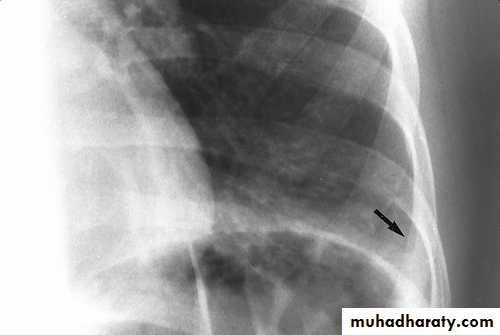

CXR: interstitial or bronchopneumonic, involve mainly the lower lobes. Bilateral diffuse infiltrates, lobar pneumonia or hilar lymphadenopathy can occur in up to 30% . Pleural effusions may occur.

Pleural effusionOther respiratory illnesses caused occasionally by M. pneumoniae include: